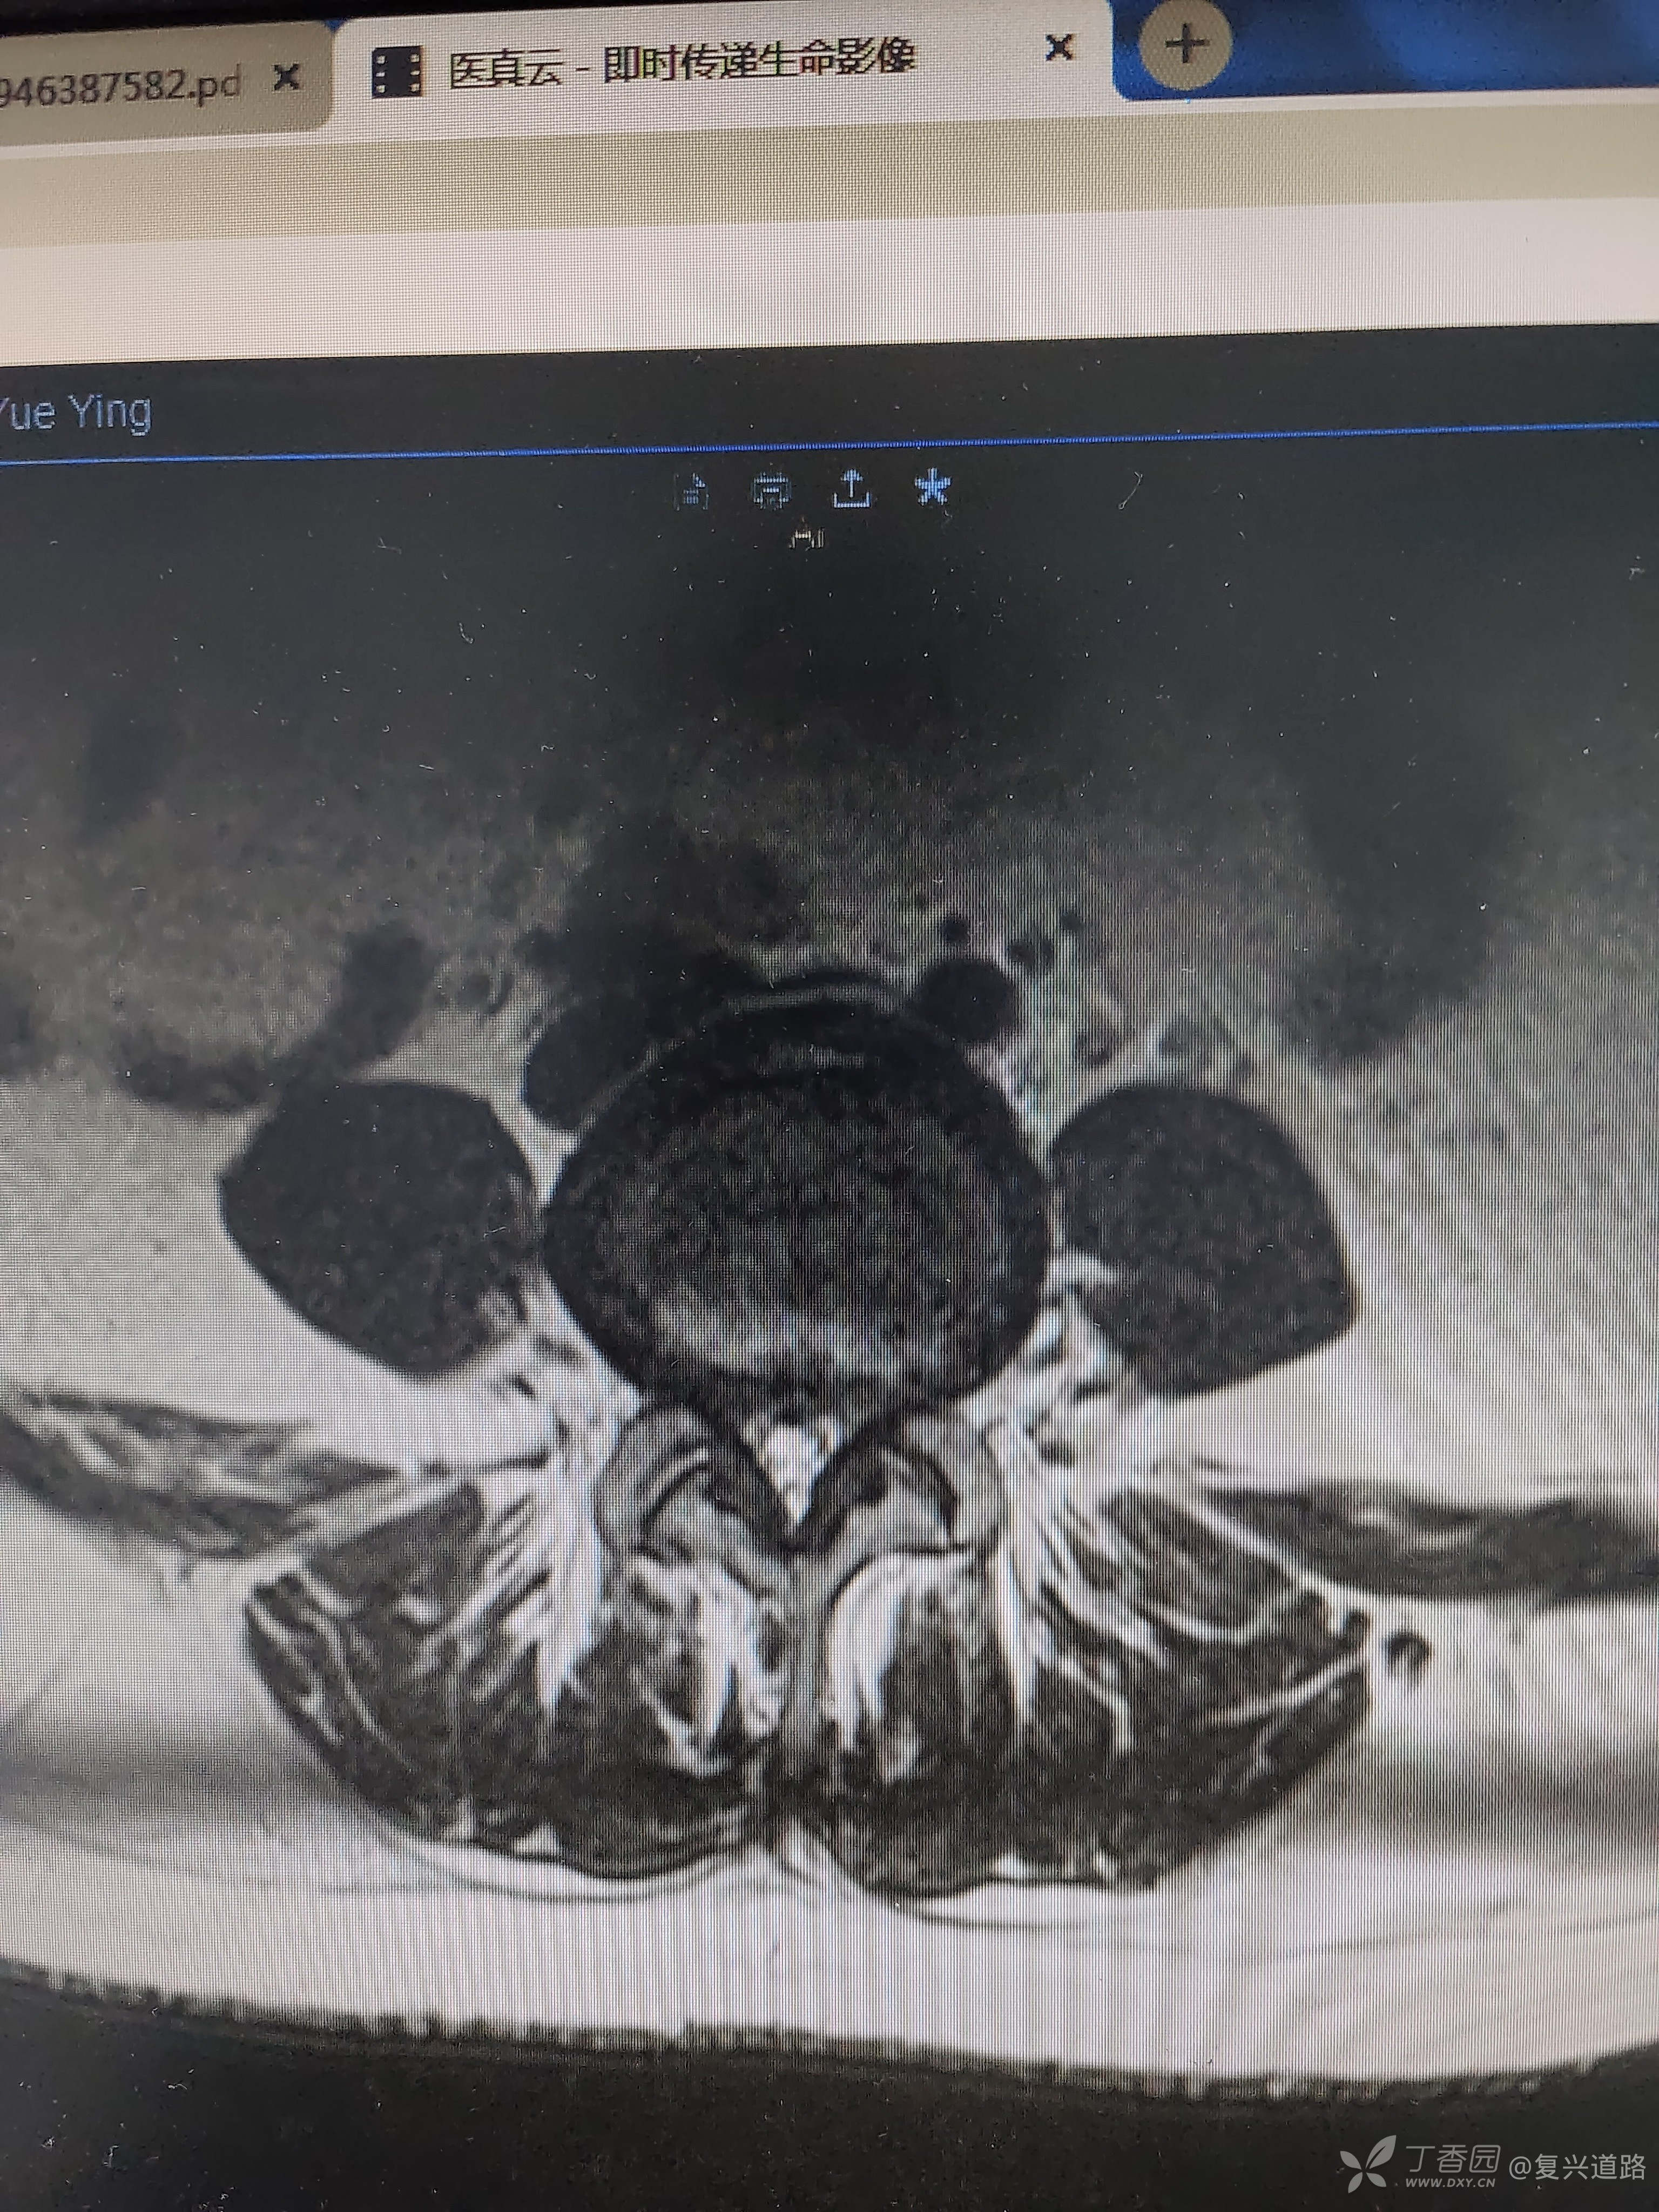

不是脊柱外科专科,今天亲戚介绍一50岁病人找我看病,诉下腰痛,伴两侧臀部胀痛,行走约1公里后左下肢痛,小腿有麻木感。体查腰臀部无明显压痛点,腰椎屈伸活动可,直腿抬高试验阴性,4字征阴性。见有症状但体征轻,考虑腰椎间盘退变,腰椎管狭窄,行磁共振检查。如上图,比较符合我的考虑。

我们基层医院腰椎管狭窄手术没怎么做,我也觉得这个病人应该先考虑保守治疗,请问保守治疗有什么有效的方法没。